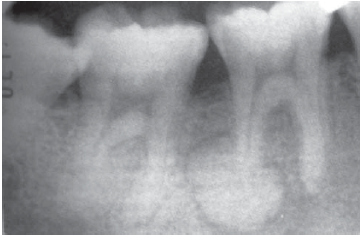

As Figuras 1 e 2 mostram radiografias periapicais do elemento 47 de um paciente que se apresentou com dor espontânea, aguda e persistente.

As Figuras 1 e 2 apresentam, respectivamente, as seguintes incidências que foram utilizadas para o auxílio de diagnóstico de fratura:

Lesão radiopaca associada à raiz distal do elemento 46.

NEVILLE BW, DAMM DD, ALLEN CM, BOUQUOT JE. Patologia oral e

maxilofacial. 3. ed. Rio de Janeiro: Elsevier, 2009. p. 657.

Paciente do sexo masculino, 25 anos, leucoderma, foi submetido a exame radiográfico periapical completo para iniciar o tratamento ortodôntico. Durante a avaliação de tal exame, o cirurgião-dentista observou uma massa radiopaca apresentando halo radiolúcido no ápice da raiz distal do dente 46 (figura acima). O teste de vitalidade pulpar indicou que esse elemento era vital.

Diante desses achados, o diagnóstico e a conduta a serem realizados são, respectivamente,